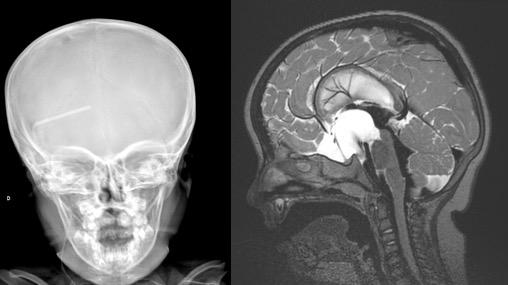

le métopisme

il est défini par la persistance de la suture métopique au delà de l’âge habituel de fermeture, ce qui pose la question de la norme. D’après notre travail, la suture métopique reste perméable au-delà de l’âge d’un an dans environ 5% de la population, après quoi sa prévalence reste stable. elle n’a pas de retentissement notable sur la morphologie cranio-faciale, néanmoins les crânes ont un « air de famille » (cf. ci-dessous) avec un bombement temporal au dessus d’un pincement ptérional.